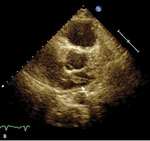

Rycina. Skrzeplina (strzałki) przechodząca do lewego przedsionka uwidoczniona w projekcji 4-jamowej (A) oraz zmodyfikowanej przymostkowej w osi krótkiej (B).

Obraz echokardiograficzny ujawnił typowe dla przeciążenia prawej komory powiększenie jej wymiaru, skrócenie czasu akceleracji wyrzutu płucnego z tzw. zazębieniami na ramieniu zstępującym oraz hiperkinezę wolnej ściany prawej komory z hipokinezą podstawnych jej segmentów i TAPSE 12 mm. Jednak najważniejszą obserwacją było stwierdzenie nieprawidłowego echa w jamie prawego przedsionka, echa odpowiadającego skrzeplinie wklinowanej w przetrwały otwór owalny (PFO) i przechodzącej do lewego przedsionka (rycina).